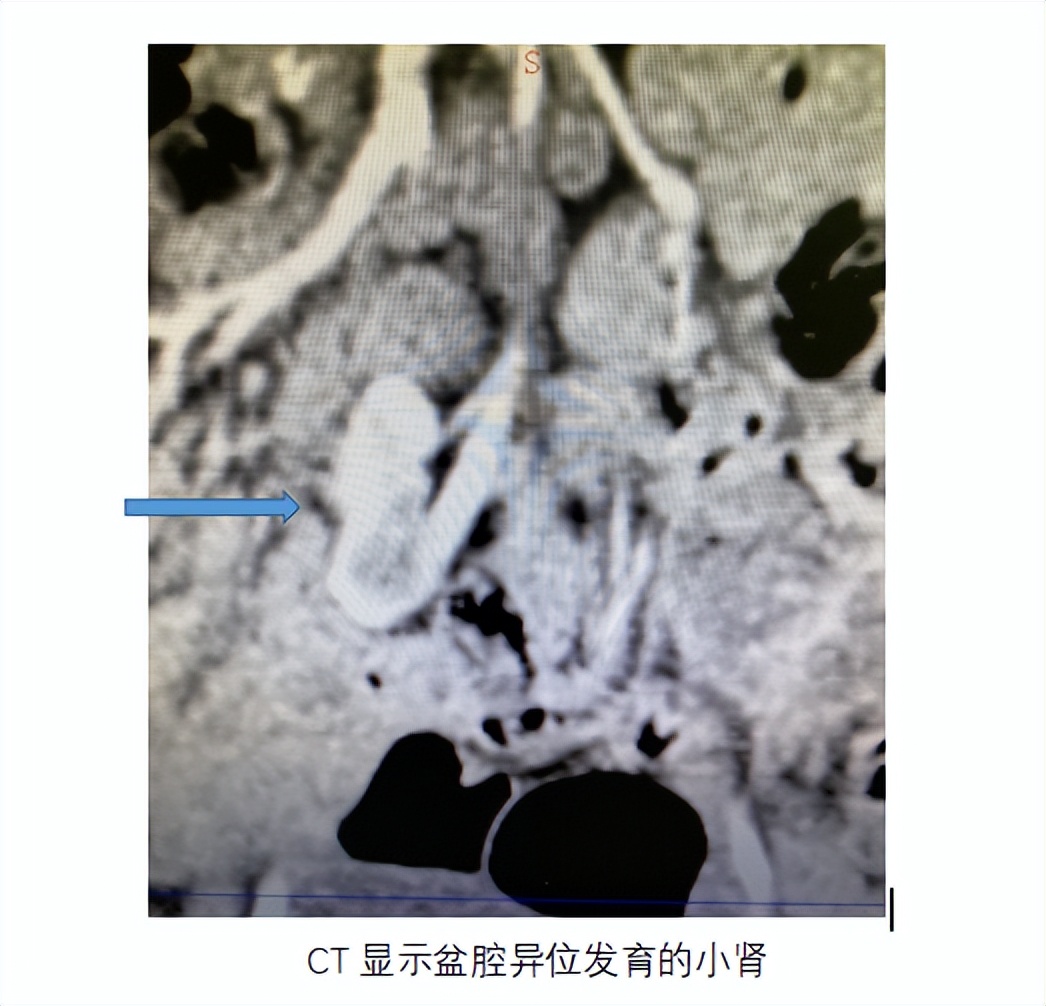

患儿为女孩,5岁,持续少量遗尿2年,自幼尿布常湿,能够正常排尿。但是,随着患儿生长,症状渐重。查体发育正常,血压正常,会阴部见大片尿疹斑,于是在本院泌尿外科就诊,超声检查发现右肾缺如,盆腔内可见未发育的异位小肾。

患儿做完手术前检查,无明显治疗禁忌,先行腹主动脉造影显示发自腹主动脉的异位肾动脉,微导管超选择入异位肾动脉,注入微球及弹簧圈行栓塞。栓塞后孩子无不适,第二天遗尿症状明显缓解。患儿妈妈的脸上也露出了久违的笑容。查完房后,办理出院。